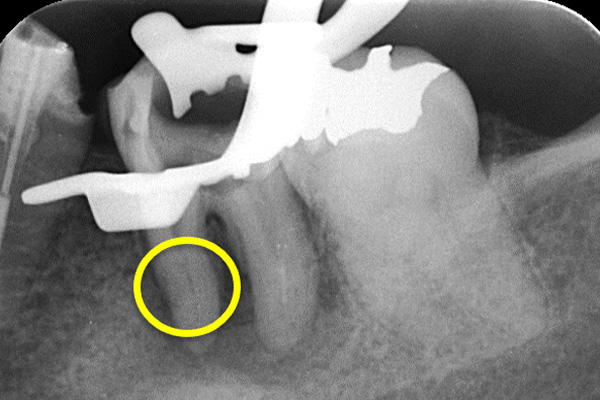

更に、拡大すると歯根破折に加え、器具の破折片も確認できる。

心臓の鼓動のように『ドク・ドク』と浸出液が出ているのが分かる。